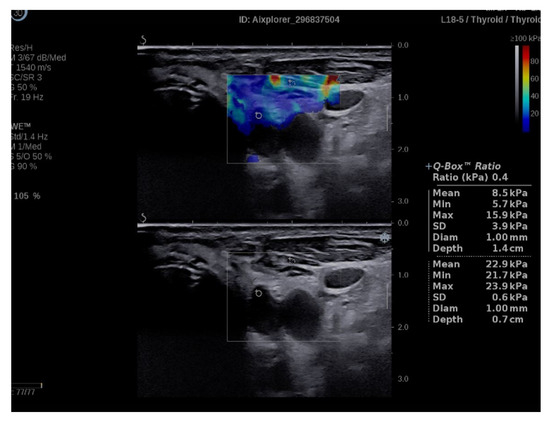

2.4. Elastography Exam

3.1. SWE Results